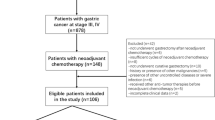

Pre-NAC clinical and imaging data of AEG patients who underwent surgical resection after preoperative-NAC at two centers were retrospectively collected from November 2014 to September 2020. The dataset included training (n = 60) and external validation groups (n = 32). Three models, including CT-based radiomics, clinical and radiomics–clinical combined models, were established to differentiate pCR (tumor regression grade (TRG) = grade 0) and nonpCR (TRG = grade 1–3) patients. For the radiomics model, tumor-region-based radiomics features in the arterial and venous phases were extracted and selected. The naïve Bayes classifier was used to establish arterial- and venous-phase radiomics models. The selected candidate clinical factors were used to establish a clinical model, which was further incorporated into the radiomics–clinical combined model. ROC analysis, calibration and decision curves were used to assess the model performance.

Clinical, pathological and CT imaging data of AEG patients who underwent surgical resection after preoperative NAC at the First Affiliated Hospital of Zhengzhou University and Henan Provincial Cancer Hospital were retrospectively collected from November 2014 to September 2020. The patient enrollment criteria included the following: (1) AEG confirmation by gastroscopic biopsy pathology prior to treatment; (2) pre-NAC clinical stage of cT2–4N0–3M0 stage; (3) NAC treatment in 2–6 cycles; (4) lack of other antitumor therapy administered before NAC; (5) enhanced CT scan obtained within 1 week prior to NAC treatment with complete imaging data; (6) lesion covering at least 3 slices on CT cross section and a maximum plane diameter of at least 2 cm; and (7) radical resection performed after NAC treatment with complete postoperative pathology data. The exclusion criteria included: (1) combined history of other malignancies; (2) poor CT image quality or lack of raw DICOM data; (3) adverse event during NAC or less than 2 cycles of NAC; (4) combined heart, lung and other important organ dysfunction in which a CT examination could not be performed; and (5) incomplete CT imaging data or clinical and pathological data.

Patients with AEG from the First Affiliated Hospital of Zhengzhou University were included in this study as the training group (n = 60), and 32 patients with AEG from Cancer Hospital of Zhengzhou University were included as the external validation group (n = 32).